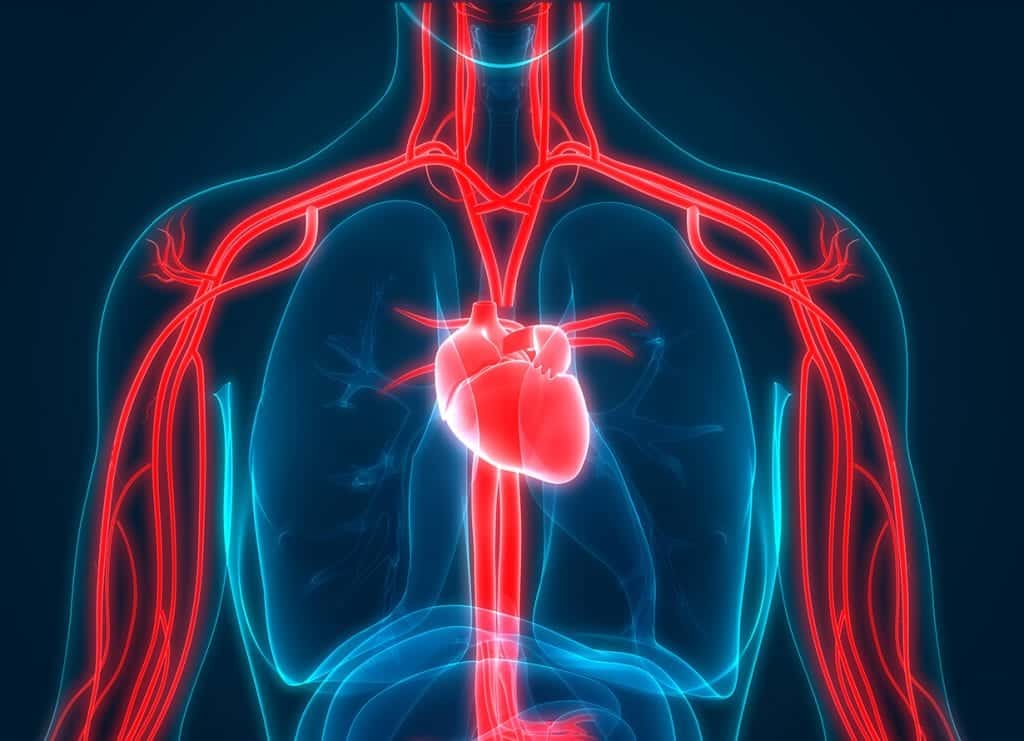

Órgãos do Sistema Cardiovascular

Os órgãos do sistema cardiovascular garantem a circulação do sangue pelo organismo e, consequentemente, o transporte de oxigênio e nutrientes para todas as células.

Coração

O coração é um órgão muscular oco formado pelo tecido muscular cardíaco. É responsável pelo bombeamento do sangue para todo o corpo por meio de contrações rítmicas involuntárias (sístole e diástole).

Vasos sanguíneos

Os vasos sanguíneos, são os canais por onde circulam o sangue pelo corpo, sendo eles:

- Artérias: responsáveis pelo transporte do sangue do coração para os tecidos;

- Veias: responsáveis pelo transporte do sangue dos tecidos para o coração;

- Capilares: vasos bastante delgados e que apresentam paredes finas, ou seja, permite a troca de substâncias entre o sangue e os tecidos.